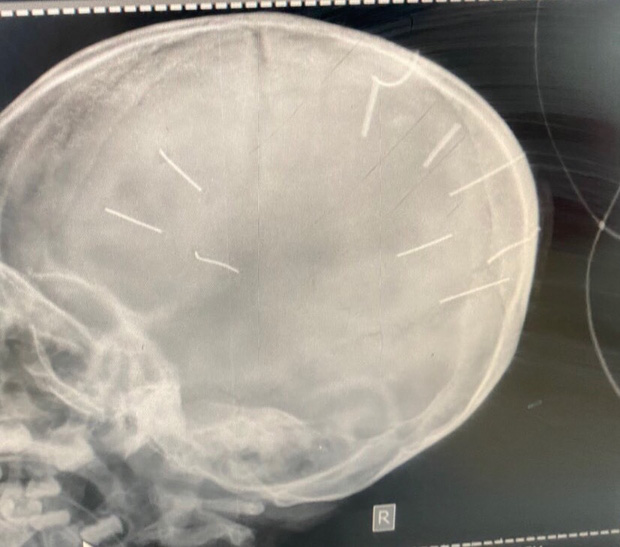

Ngày 19/1, Công an TP. Hà Nội phối hợp với phòng Cảnh sát hình sự (PC02) và các phòng nghiệp vụ thuộc Cục Cảnh sát hình sự (C02) Bộ Công an điều tra, làm rõ vụ việc bé gái Đ.N.A., 3 tuổi nghi bị bạo hành, có 9 dị vật nghi là đinh trong sọ não.

Hình ảnh chụp X-Quang hộp sọ bệnh nhân với 9 hình thể nghi là đinh (Ảnh: Bệnh viện Đa khoa huyện Thạch Thất cung cấp)

Bệnh viện Đa khoa Xanh Pôn đã tiến hành chụp cắt lớp dựng hình, nhận thấy có những hình ảnh giống như đinh gỗ ở sọ và tổ chức não, tổng cộng 9 cái.